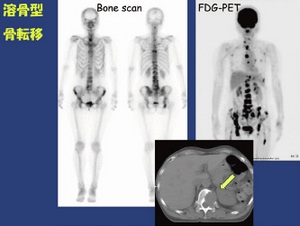

全身骨シンチグラフィ 乳癌 肺癌 前立腺癌等の骨転移病巣の検出

骨シンチグラフィによる骨転移の診断 Bone Scan Ct Mri画像診断